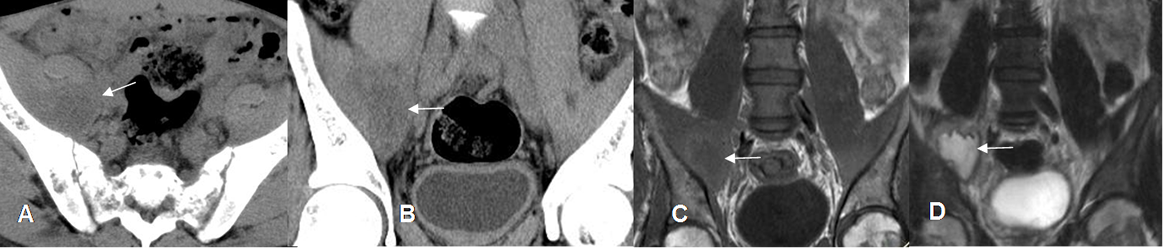

Fig 147 B. Absceso del psoas.

A: TAC axial, B: TAC reconstrucción coronal, C: RM coronal en T2y D: RM coronal en T1. Engrosamiento del músculo iliopsoas, con imagen hipointensa en la TAC, hipointensa en T1 e hiperintensa en T2, que corresponde a absceso del psoas.